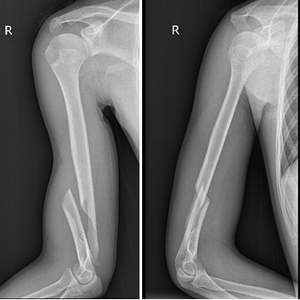

主治医师唐聪给小强申请了影像检查

检查结果显示

他的右肱骨下段螺旋性骨折

骨头错位明显

X光可见小强的右肱骨下段出现骨折。